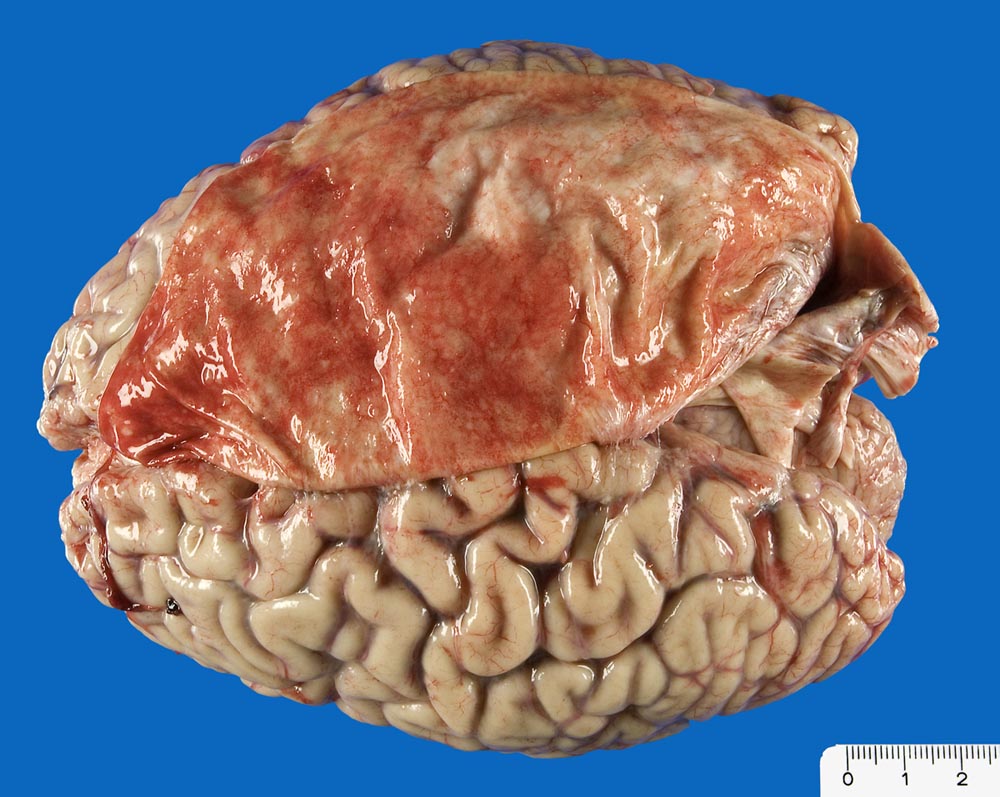

Mammakarzinom: Meningeosis carcinomatosa

Starke Gefässhyperämie der weichen und harten Hirnhaut. Meningeosis carcinomatosa: zahlreiche weisse flache Knötchen.

Skelettmetastasen in der Wirbelsäule von zervikal bis sakral sowie des Sternums mit Verdrängung der Hämatopoese. Minimale Restanteile des hämatopoetisch aktiven Knochenmarks (Thrombopenie laut klinischen Angaben). Metastasenleber mit sekundären ischämischen Infarkten. Hämangiosis carcinomatosa des Myokards. Lymphangiosis carcinomatosa der Lungen, des Myokards und des Perikards. Nervenscheideninfiltration des Tumors in der Pleura. Pleurakarzinose (Pleuraerguss rechts: 750ml).

Mässig differenziertes invasiv duktales Mammakarzinom (pT2 pN1 G2). Ablatio mammae vor 14 Jahren. Brustwandrezidiv und Radiotherapie (50 Gy) vor 6 Jahren.